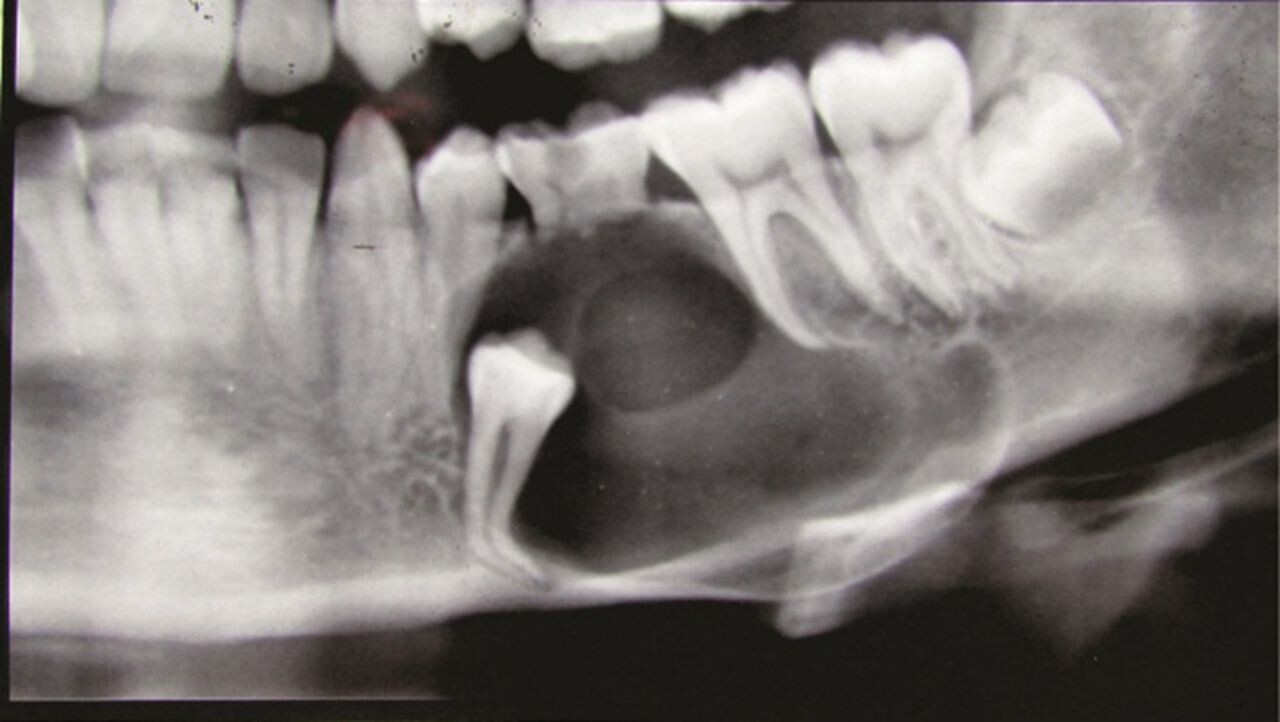

Formation of Cysts or Tumours

If the wisdom teeth problems are not dealt in an appropriate manner, the tooth will develop a sac within the jawbone. This sac has the ability to fill with fluid, which gradually develops into the formation of cyst, damaging the teeth, jawbone, and nerves. There are chances that this cyst could progressively develop into a tumour if untreated which could ultimately result in the removal of tissue and jaw bones.